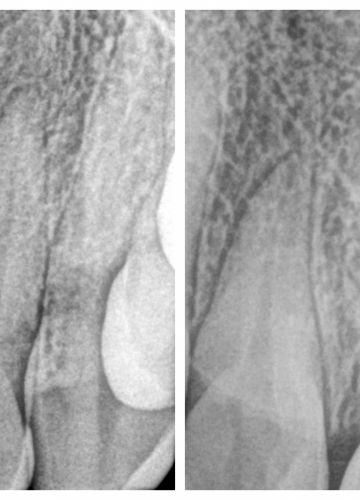

• Neatjaunojama zoba atraumatiska ekstrakcija (izraušana)

• Tūlītēja zoba implanta ievietošana un pagaidu kronīša (plastmasa) izgatavošana.